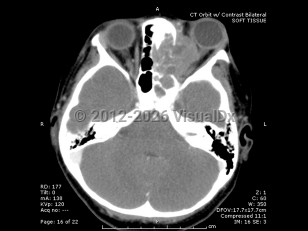

Rhabdomyosarcoma is a rare childhood cancer that affects approximately 350 children per year in the United States, with 10% of cases involving the orbit. Rhabdomyosarcoma is the most common primary orbital tumor in childhood. Patients usually present between 5 and 10 years of age, with boys having a higher incidence than girls.

Orbital rhabdomyosarcoma develops from undifferentiated mesenchymal cells that have the capacity to become striated muscle. There are several histopathologic types, including embryonal (the most common form) and alveolar (which carries the worst prognosis).

Proptosis is the most common presenting sign and may develop over the course of just a few days or a month. Often there is a history of recent trauma upon presentation of the tumor, which may lead to confusion with the diagnosis. Orbital rhabdomyosarcoma sometimes presents with strabismus or as a localized eyelid or conjunctival mass.